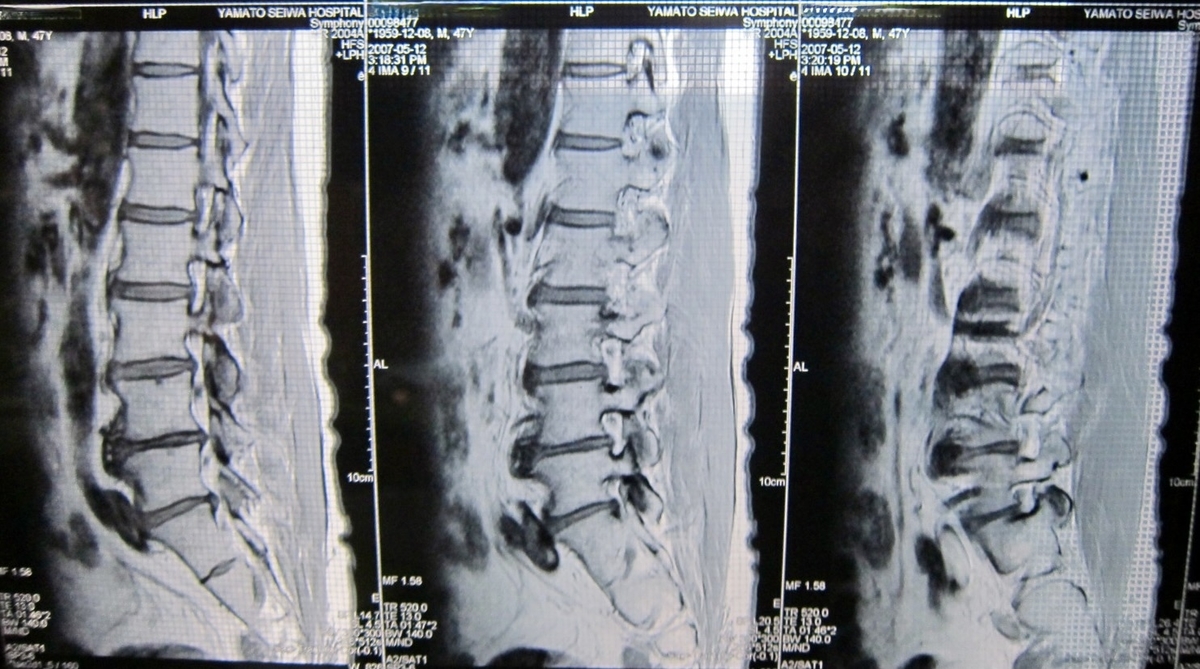

40代後半に椎間板ヘルニアが悪化して精密検査を受けているが、ここにきて当時と同じような症状が出始めている。走ることがイマイチなのは、このことだけが原因ではないと思うが…。

その時のレントゲン画像(2007年)

手足の痺れぐらいなら我慢できるが、これ以上に痛みが出るとちょっとね。